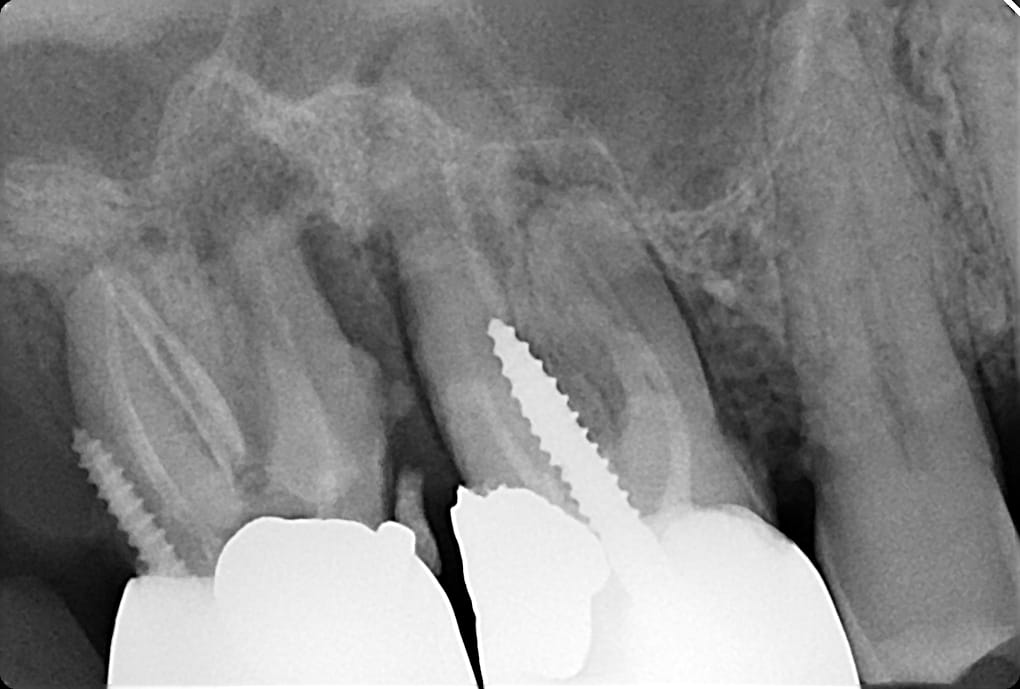

Admirez le parallélisme... l'aéro-intégration...

Si l'ancrage radiculaire n'est pas dans la racine, peut on toujours parler d'ancrage radiculaire ?

oui car c'est pas ecrit intra canalaire et donc une fausse route est un ancrage radiculaire ,ils avaient cas etre precis :)

serieusement c'est quoi cette difference d'opacite des tenons